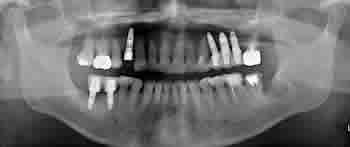

親知らず症例 ⑨

| 治療前 | 治療後 |